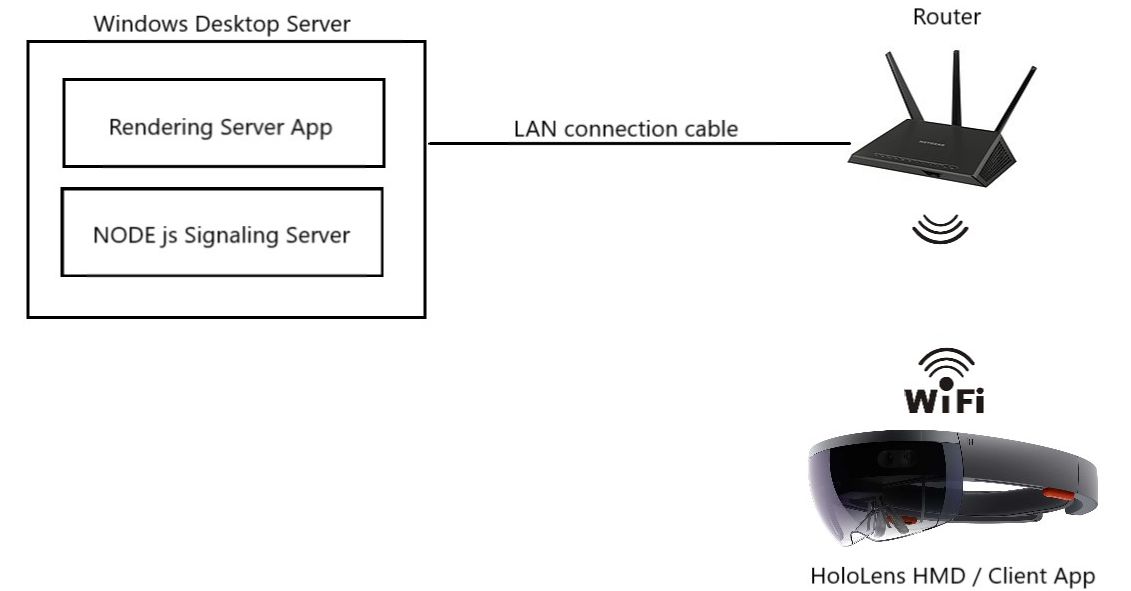

As a result, our visualization architecture comprises three interconnected applications, running in the same time: the Hololens Client, the Windows Desktop Server, and a Signaling Server which manages the communication and connection between the first two, as depicted in Figure 4.2.

Concerning the hardware architecture, it comprises 3 components: a Router, the Desktop Windows Server (hosting the Rendering Server app and the Signaling Server app), and the HololeLens HMD running the DirectX HoloLens Client. The hardware architecture is presented in Figure 4.4.

For reasons such as control, reliability, transmission speed and latency we have preferred to use for communication the local network instead of the internet.

The peers interact with the signaling server to share the handshakes and start a direct peer-to-peer transmission. After this point, the actual data is sent directly between client and server. While the traffic and computation load of the signaling server is low, it is still a core component of the WebRTC connection architecture. To simplify the overall architecture and improve communication speed, we have deployed the signaling server on the same windows desktop machine that runs the Rendering Server.

The signaling server code is node.js and is started with the simple command "node ./server.js".

4.1.2 Client

This is a simple DirectX client which connects to the Signaling Server for handshaking, to finally establish a peer-to-peer connection with the Rendering Server via WiFi in order to receive the rendered frames as a stream, and send back to the Rendering Server updates concerning the HMD’s position and rotation via the dedicated data channel. The Rendering Server updates the view per the newly received coordinates of the HoloLens HMD in the world.